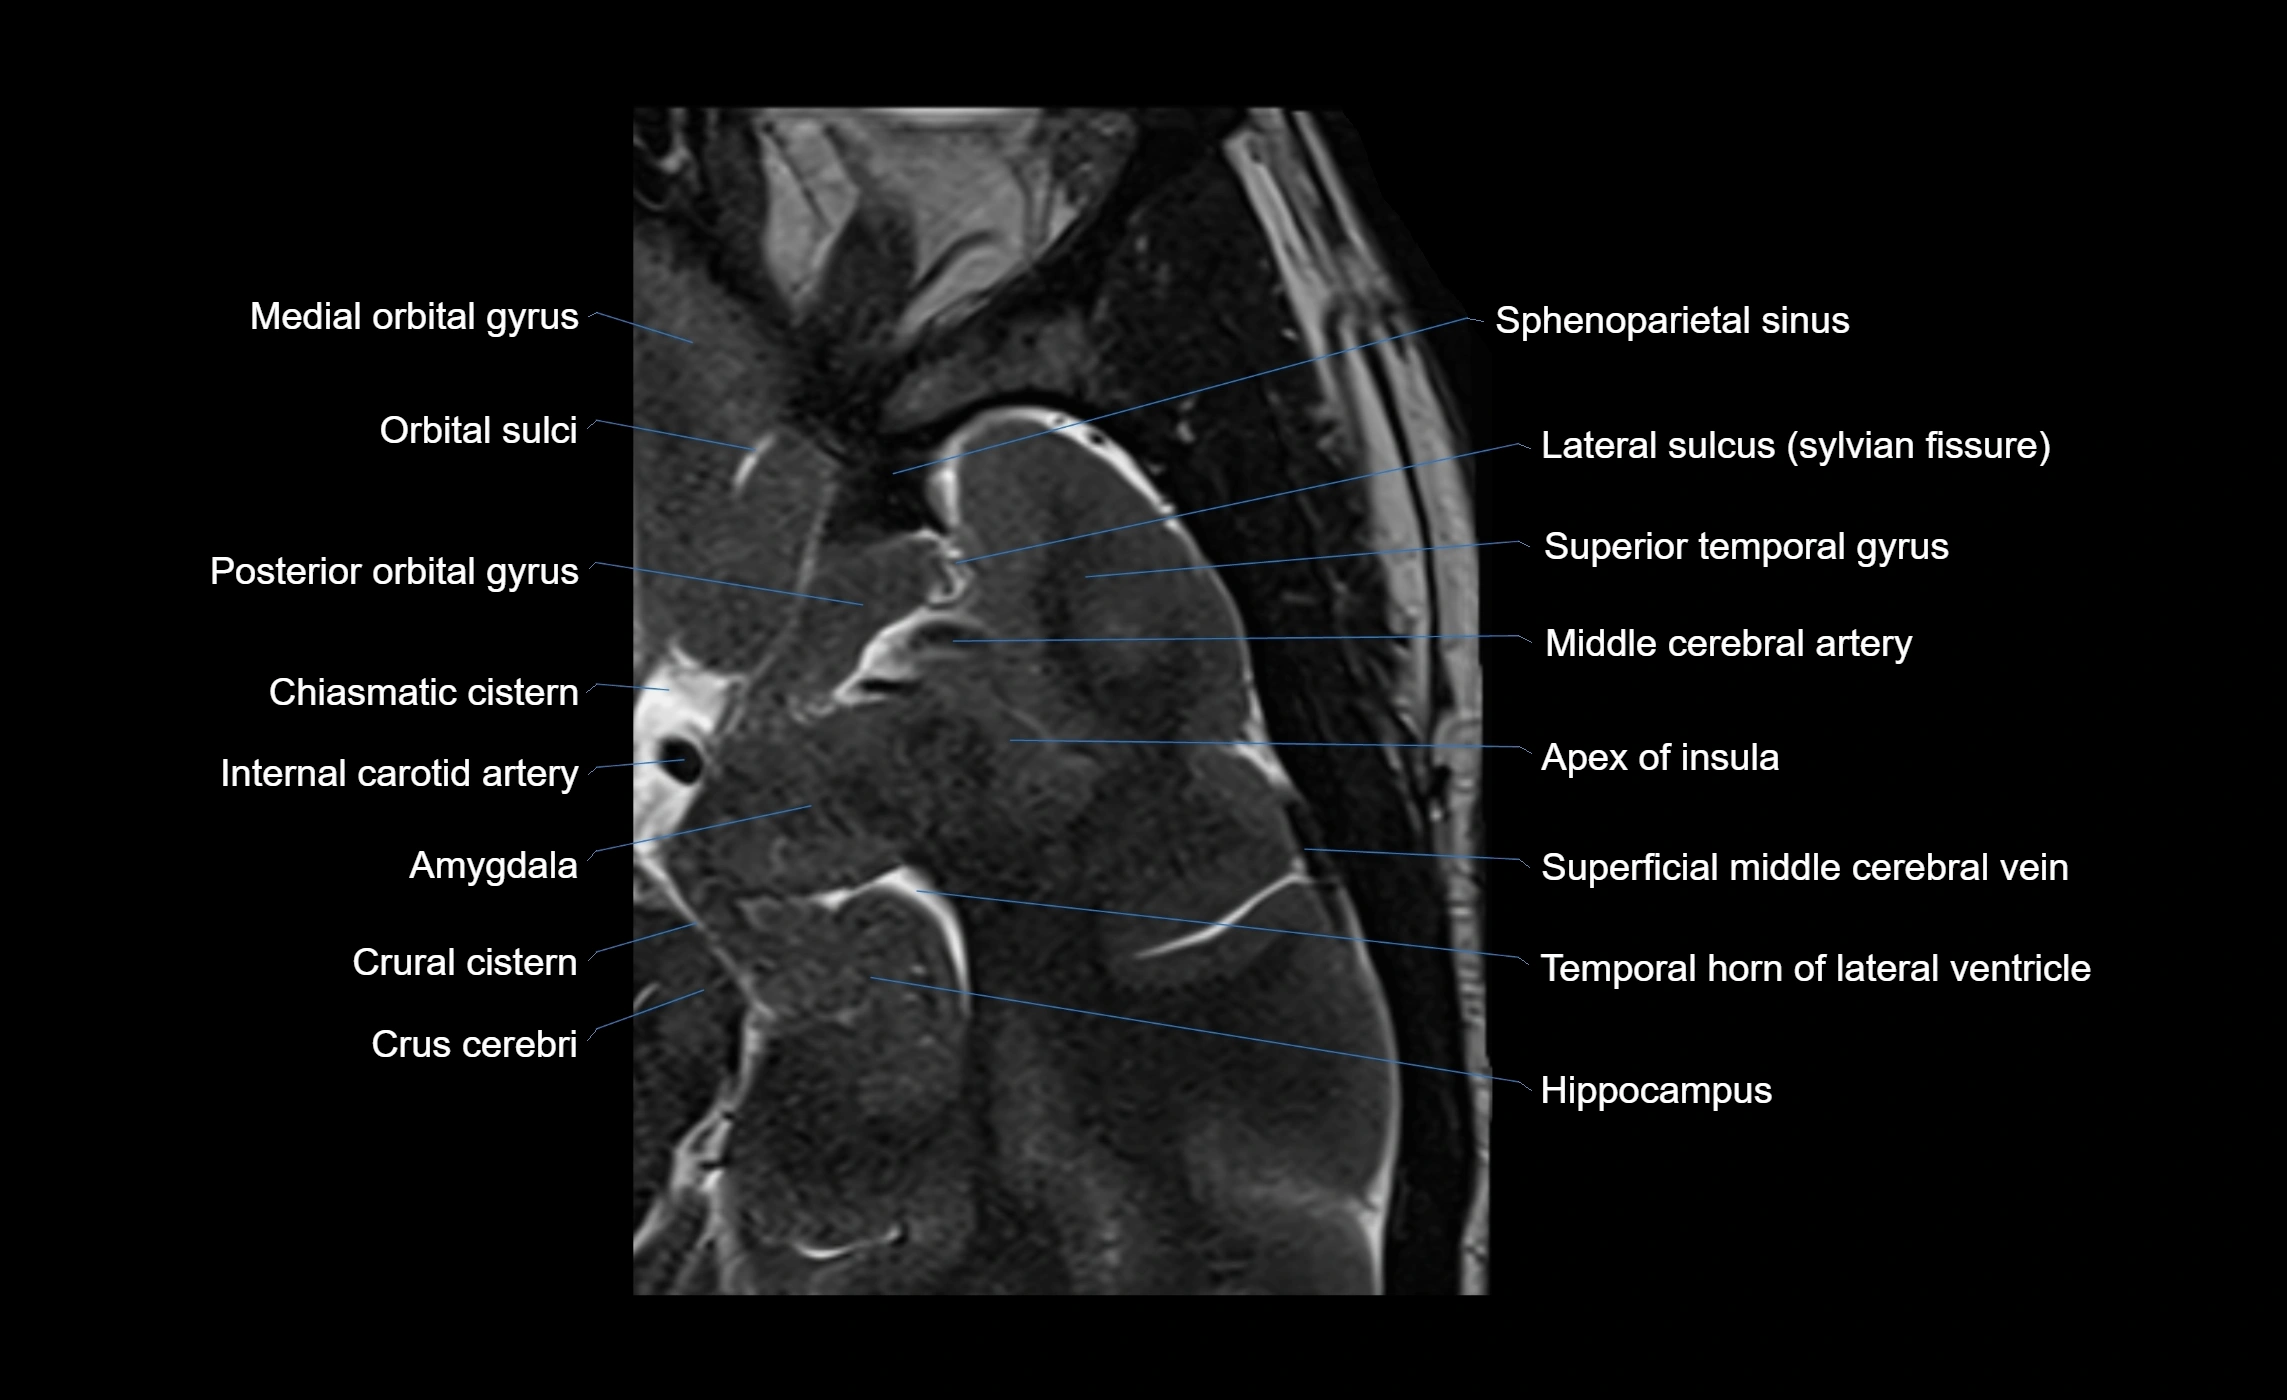

The anterior ascending ramus of the Sylvian fissure is a significant anatomical landmark in the lateral surface of the cerebral hemisphere. It represents one of the key branches of the Sylvian fissure (also known as the lateral sulcus) and plays an essential role in demarcating the boundaries between important cortical regions, notably within the frontal and parietal lobes. Understanding its anatomy and imaging appearance is crucial in neuroradiology, neurosurgery, and neuroanatomy for accurate localization and identification of adjacent brain structures.

• Supplied predominantly by branches of the middle cerebral artery (MCA), particularly its opercular branches.

• The MCA runs within the Sylvian fissure and provides small cortical branches to adjacent gyri and sulci.

Venous Drainage

• Drained by superficial Sylvian veins (also called superficial middle cerebral veins), which follow the course of the Sylvian fissure.

• Venous blood ultimately drains into the sphenoparietal sinus and cavernous sinus.

MRI Appearance

• T1-weighted imaging:

• The Sylvian fissure and its anterior ascending ramus appear as low-signal intensity (dark) CSF-filled clefts between the gyri.

• Clear demarcation between adjacent gray and white matter.

• T2-weighted imaging:

• The fissure, including the anterior ascending ramus, is hyperintense (bright) due to CSF signal.

• Better visualization of the separation between opercular and triangular parts of the inferior frontal gyrus.

• FLAIR imaging:

• The ramus is visualized as a linear dark space (suppressed CSF signal) between the surrounding cortex.

• Adjacent cortical and subcortical abnormalities (e.g., edema or gliosis) can be assessed relative to the ramus.